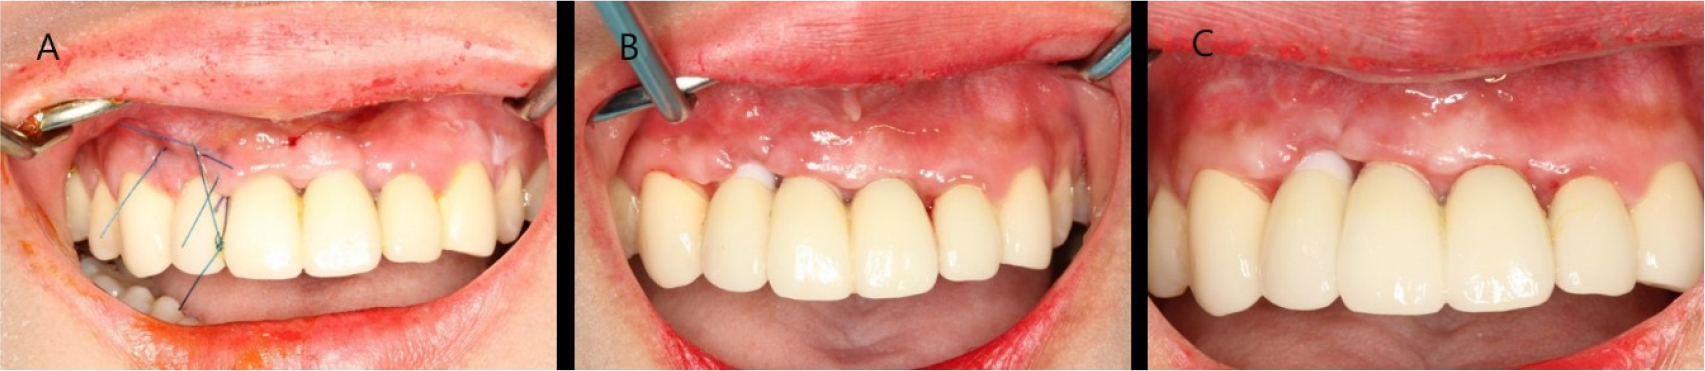

The stitches were removed after 2 weeks. Normal healing took place without any adverse events. Complete abutment coverage did not occur, but the gingiva was thickened through soft tissue augmentation (Fig. 3). At the 3-year follow-up, gingival creeping had occurred. Furthermore, the fixture was not visible because the buccal gingiva had thickened, and peri-implant tissues had remained healthy (Fig. 4).